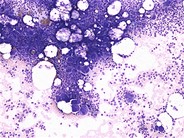

Idiopathic Thrombocytopenic Purpura - 2. Idiopathic Thrombocytopenic Purpura - 4. Immune Thrombocytopenia (ITP): Background, Pathophysiology, Etiology Giant thrombocyte in peripheral blood smear of an ITP patient ... Idiopathic Thrombocytopenic Purpura Smear